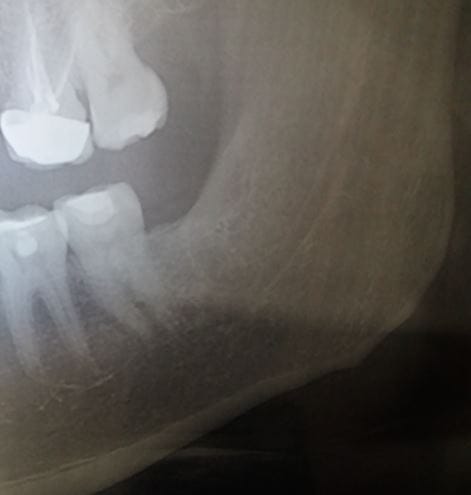

En Agosto me extrajeron la última muela del juicio (inferior derecha). Era la que mejor tenía y por eso se quedó para la última. No me molestaba en absoluto pero mi odontólogo me recomendó sacarla porque estaba totalmente rodeada de encía y hacía difícil su limpieza, riesgo de infecciones, etc. La extracción apenas duró 1 minuto y el odontólogo me comentó que estaba muy "agarrada" pero que todo fue bien. Pasaron los días y tenía mucho dolor que se irradiaba hacia el cuello. Me comentaron en la revisión que tenía una alveolitis y se terminó pasando a los 15-20 días. Tras esto y voy al meollo de la cuestión, me noté en la parte interior de la mandíbula como un bulto a la altura del alveolo de la muela extraída. Si pasas el dedo por la línea de la mandíbula interior, al llegar a ese punto se nota como un resalto en el hueso. No me produce un dolor enorme, pero sí una molestia continuada en esa zona, como si tuviera algo por dentro presionando la encía. Volví al dentista y me dijo que era el hueso de la mandíbula y que con casi toda seguridad se reabsorbería con el paso del tiempo, que no le diera importancia. Que en el caso de no re absorberse me abrirían la encía y lo pulirían sin problema para que la línea de la mandíbula volviera a estar lisa. Han pasado 6 meses y tras no ver progreso alguno y continuar con molestias constantes en la zona del bulto volví al odontólogo que comprobó que el agujero que había dejado la muela ya estaba cubierto completamente y me hizo una radiografía en la que se veía que todo estaba correcto, el hueso ya se había formado donde antes estaba la muela. Le pregunté si ese bulto lo había tenido siempre o me había salido a raíz de la extracción. Me explicó que a veces pasa en las extracciones que el hueso mandibular se puede astillar al hacer fuerza para la extracción, y que seguramente eso era lo que había pasado. Me propuso limar el hueso, creo que lo llamó “regularizar el reborde alveolar a nivel del 48”, pero esta vez me lo puso peor que 6 meses atrás donde parecía algo rutinario, me advirtieron que no era tan simple al pasar el nervio lingual por debajo, que había ciertos riesgos. Acepté con tal de quitarme esta molestia continua. La cirugía fue bien, pero han pasado 2 semanas y noto que sigo teniendo resalto a la altura del alveolo (menos que antes) y me sigue molestando. He ido a la revisión y me han dicho que es normal, que deje pasar tiempo y seguro que se regulariza sólo. Sobre todo me dicen que no me toque el resalto con la lengua, algo casi imposible, ya que se me va constantemente a ese punto, no puedo evitarlo. Empiezo a estar un poco angustiado y bastante nervioso. ¿Me recomendáis que siga esperando varios meses más a ver si mejora sólo tras esta última cirugía o deberían volver a abrir la encía y limar el hueso más? ¿Es verdad que el reborde alveolar o bulto que noto en la encía con el paso del tiempo irá desapareciendo?